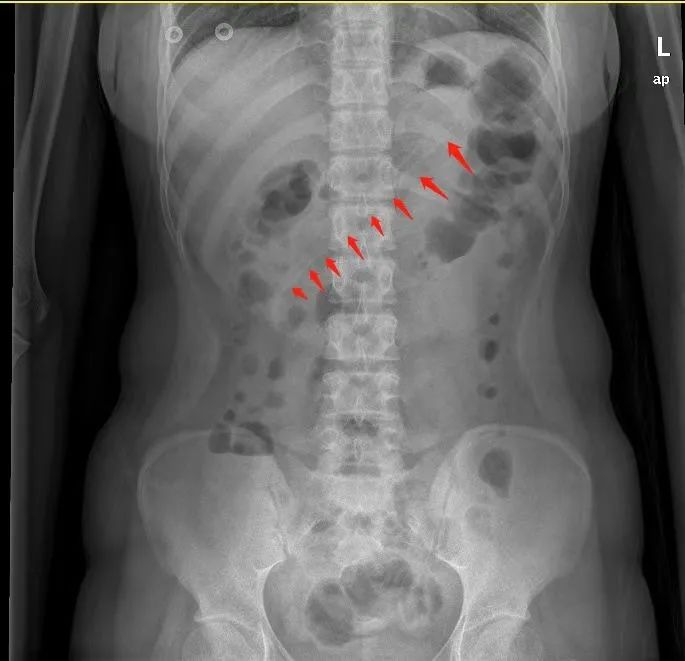

腹部X线检查显示,小李胃中的勺子长达17厘米,因此胃镜下取异物有较大的难度。但如果不取出,患者可能会出现消化道梗阻、出血和穿孔等并发症。因此,胃镜下取出异物势在必行。

术前,黄晓春主任进行了充分的术前告知后,患者及家属签字同意。与此同时,胃镜室与麻醉科也提前拟定了多个可能的方案,并知会耳鼻喉科和胃肠外科做好准备。术中,实施无痛麻醉后,在医生操作下,胃镜快速就位。通过胃镜,一进入胃腔就能看到一根长长的塑料勺子横跨在胃体至十二指肠球部。

黄晓春主任一开始选择用异物钳钳夹异物,但因为太大了无法夹住,给手术进行带来了一定难度。随后,她改用圈套器,尝试套住异物。但因异物两端顶住胃腔和十二指肠球腔,要想套住异物并不容易。经过不断地调整圈套的方向,终于套住了勺子合适的位置,顺着胃食管纵轴缓缓取出。

历经40分钟,一根长约17cm的粉色塑料勺子终于从胃内取出了。手术圆满结束后,患者家属悬着的一颗心也放下了,并向医务人员竖起大拇指点赞。